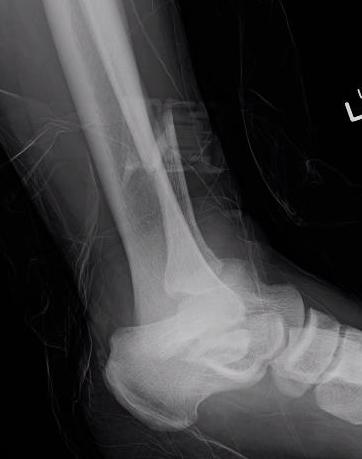

X-ray assessment

3 standard views

AP / Lateral / Mortise

Mortise

- AP with foot internally rotated

- should be symmetrical space around talus

Ankle Mortise ViewMortise

Ankle AP Xray Syndesmotic Measurements Ankle Mortice Xray Syndesmotic Measurements Mortise

Tibia / fibular overlap < 1mm / syndesmotic injury

Ankle Fracture Syndesmosis WidenedAnkle Diastasis